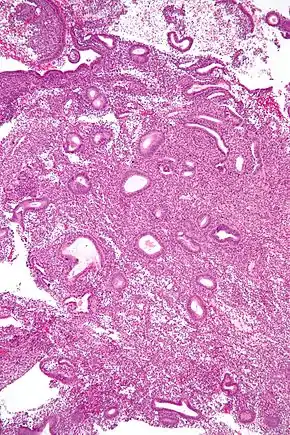

Micrograph showing an endometrial biopsy with simple endometrial hyperplasia, where the gland-to-stroma ratio is preserved but the glands have an irregular shape and/or are dilated. H&E stain. | |